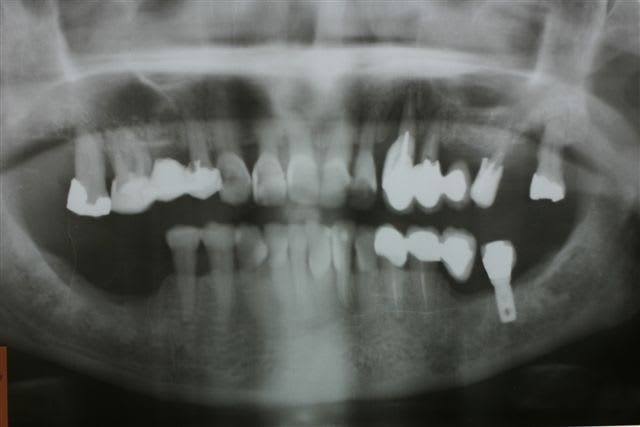

1er cas : une patiente qui perd trois implants sur 4 en zone 47 46 37 36... Elle m apporte son dentascan avec les implants en place en train de foirer

Que voit on ???

1. des implants posés bcp trop lingual ds un os très blanc donc très cortical avec une médullaire rare

2. implants courts de gros diamètre avec macrospires très agressives

3. aucune préparation du site par ostéotension

4. pas d arrêt tabagique demandé

5. après intégration pose de couronnes définitives céramiques en unitaire

Elle est arrivée avec les implants explusés depuis plusieurs mois

Un seul avait pris donc bon signe on peut y retourner

Son prat lui avait posé un bridge 34 35 extension distale 36

Secteur 40 : je lui ai posé deux monodisk en enfoui parfaitement pris et tjs équipé de leur dents provisoires métal résine depuis 5 ans